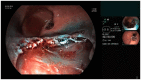

Objective: Clinical evaluation of a novel, non-thermal resection device (EndoRotor®) in the treatment of non-neoplastic Barrett's esophagus was conducted.

Methods: Fourteen patients with early Barrett's carcinoma were treated with endoscopic resection. Subsequently, EndoRotor® therapy was performed for resection of the remaining Barrett's mucosa. Complications were assessed during the study. After a three-month period patients received follow-up endoscopy to evaluate post-therapeutic stenosis.

Results: On average, 674 mm2 (172 mm2 - 1600 mm2) of Barrett's mucosa was treated with the novel device. In six (37.5%) cases, intra-procedural bleeding occurred with the need for hemostasis. All bleeding could be managed by endoscopic therapy alone. After a three-month follow-up there was no post-therapeutic stenosis registered.